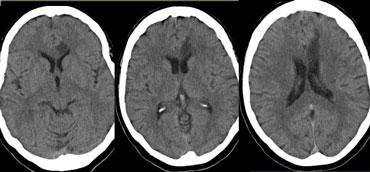

Bên trái là ba lát cắt CT liên tiếp của bệnh nhân tắc động mạch cảnh trong phải.

Tình trạng giảm tưới máu bán cầu phải dẫn đến nhiều ổ nhồi máu vùng ranh giới sâu.

Hình thái nhồi máu vùng ranh giới sâu này khá phổ biến và cần thôi thúc người đọc tiến hành khảo sát các động mạch cảnh.

Bên trái là hình ảnh của bệnh nhân có các ổ nhồi máu nhỏ ở bán cầu phải tại vùng ranh giới sâu (đầu mũi tên màu xanh lam) và tại vùng ranh giới vỏ não giữa lãnh thổ ĐM não giữa (MCA) và ĐM não sau (PCA) (mũi tên màu vàng).

Có bất thường tín hiệu tại động mạch cảnh phải (mũi tên màu đỏ) do hậu quả của tắc mạch.

Ở những bệnh nhân có các bất thường gợi ý nhồi máu vùng ranh giới, cần luôn khảo sát hình ảnh động mạch cảnh để tìm kiếm bất thường tín hiệu.